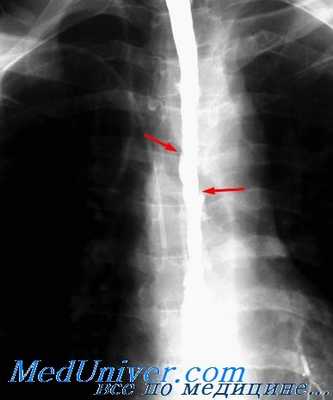

Иногда можно отметить, что назогастральный зонд лежит вне пищевода. Рентгенологи предпочитают выполнять пероральное рентгеноконтрастное исследование с гастрографином, так как боятся загрязнения барием. Однако с гастрографином можно пропустить до 15% перфораций, и поэтому, если результат отрицательный, следом должен применяться барий. Мы предпочитаем изначально использовать «разбавленный» барий. Преимущество контрастного исследования состоит в том, что оно подтверждает местоположение утечки, указывает, из какой стороны пищевода она преимущественно происходит, а также определяет, есть ли значительная стриктура или другая патология, которой тоже следует заняться.

При обзорной рентгенографии грудной клетки и брюшной полости выявляется скопление газа в средостении (пневмомедиастинум) и параэзофагеальном пространстве, гидропневмоторакс. Проведение рентгенографии пищевода с водорастворимым контрастом позволяет увидеть выход вещества за пределы эзофагеальной стенки и уточнить место разрыва пищевода. В сомнительных случаях выполняется фарингоскопия, эзофагоскопия, медиастиноскопия.

При подозрении на перфорацию пищевода в первую очередь необходимо провести обзорную рентгенографию органов грудной клетки и брюшной полости: они выявят жидкость и воздух в плевральных полостях и брюшной полости, эмфизематозность клетчатки средостения и шеи. Для выявления локализации дефекта в пищевод вводится водорастворимый контраст, и производятся снимки в положениях на спине, на животе, на боку. Миграция контрастного вещества в околопищеводную клетчатку позволит определить локализацию и размеры перфорации пищевода.